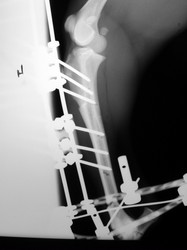

Fijación Externa

PRÁCTICAS CURSO DE FIJACIÓN EXTERNA PERFECCIONAMIENTO.

Híbrido.